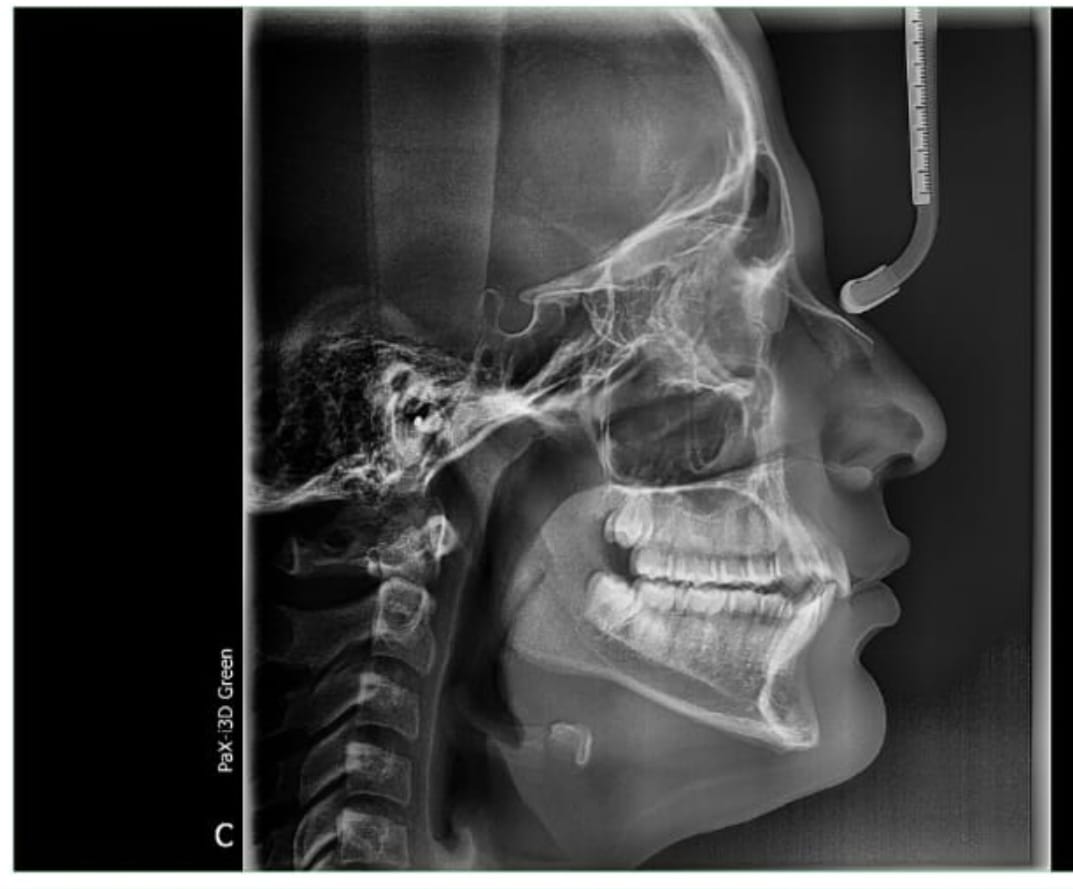

Guys , how do orthodontists actually check up if u have a narrow palate or not . Cuz Iam quite sure I have one . My paltal width is about 27 mm on a paper . Got actally diagnosed with it by an orthodontist how some how " hid it " without using an actuall paltal expander .

Like how do they even check ?